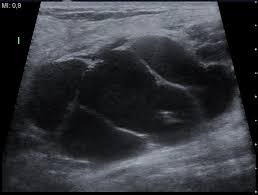

2) 플라크(죽상경화)

혈관 벽에 콜레스테롤이 쌓여 딱딱한 덩어리가 형성된 상태를 플라크라고 합니다. 이는 동맥경화의 대표적인 신호로, 심혈관 질환 위험을 예측하는 중요한 지표로 활용됩니다.